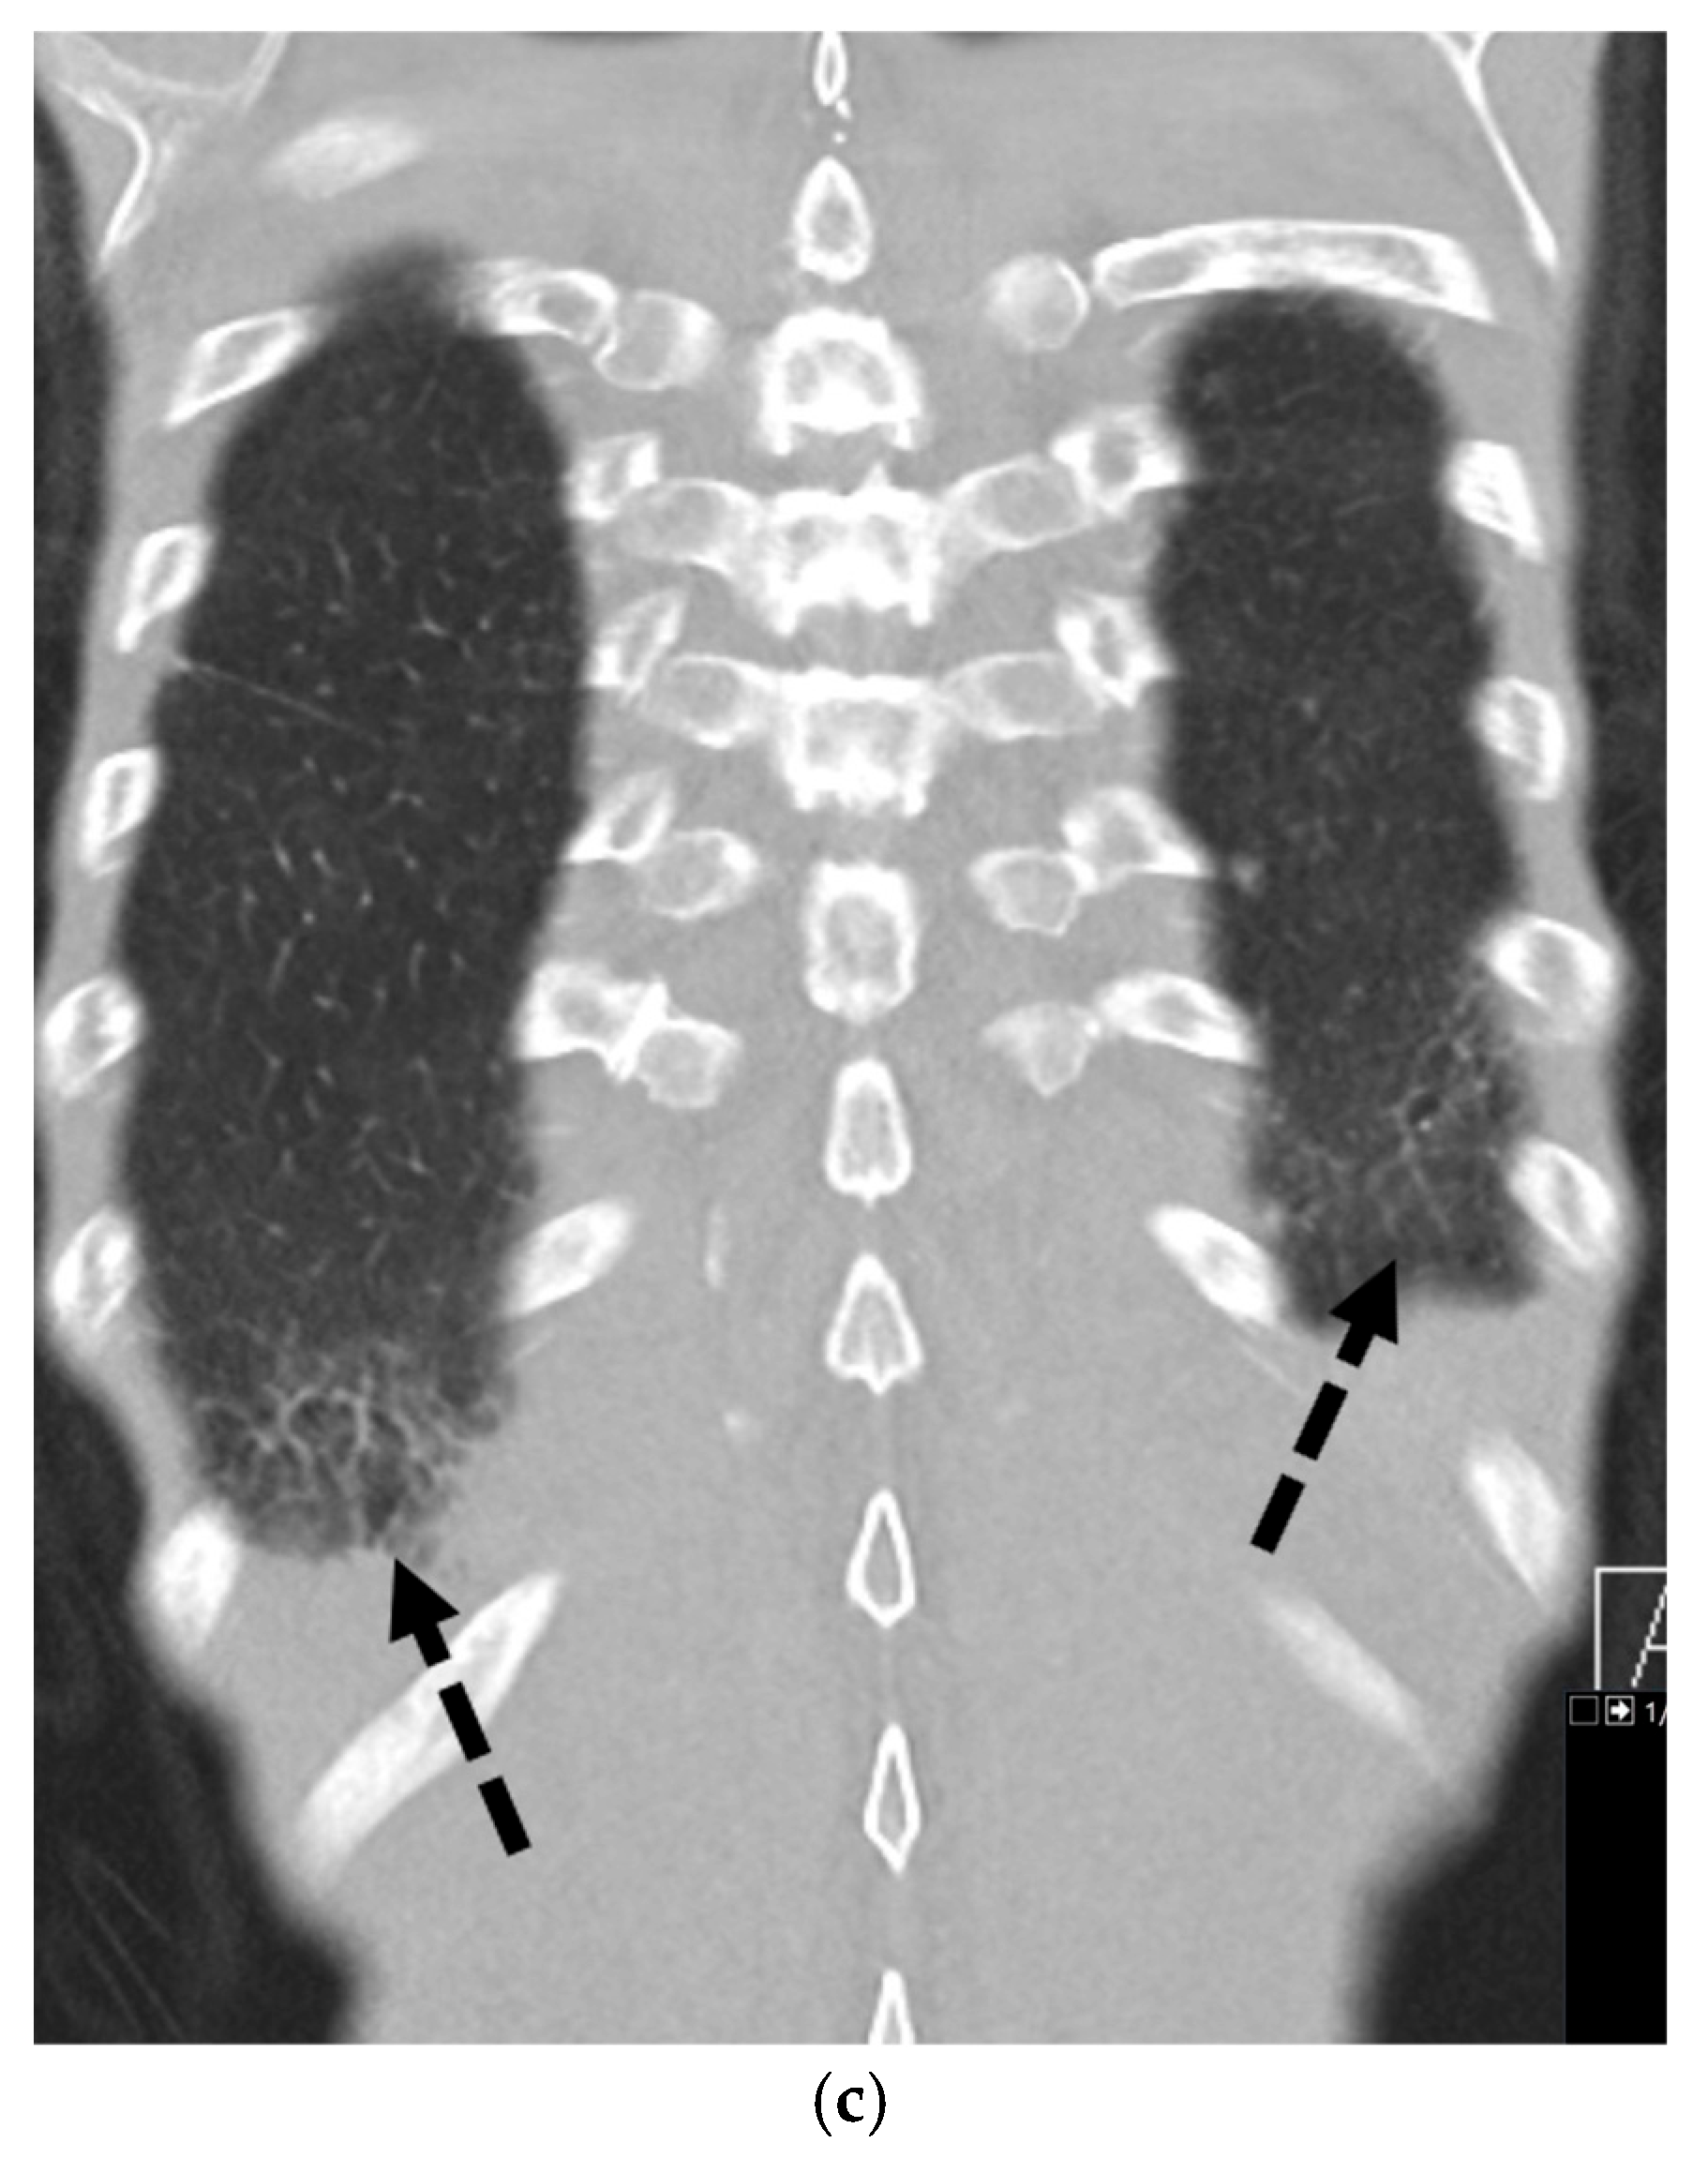

5.6.3. Ankylosing Spondylitis

5.6.4. Marfan’s Syndrome